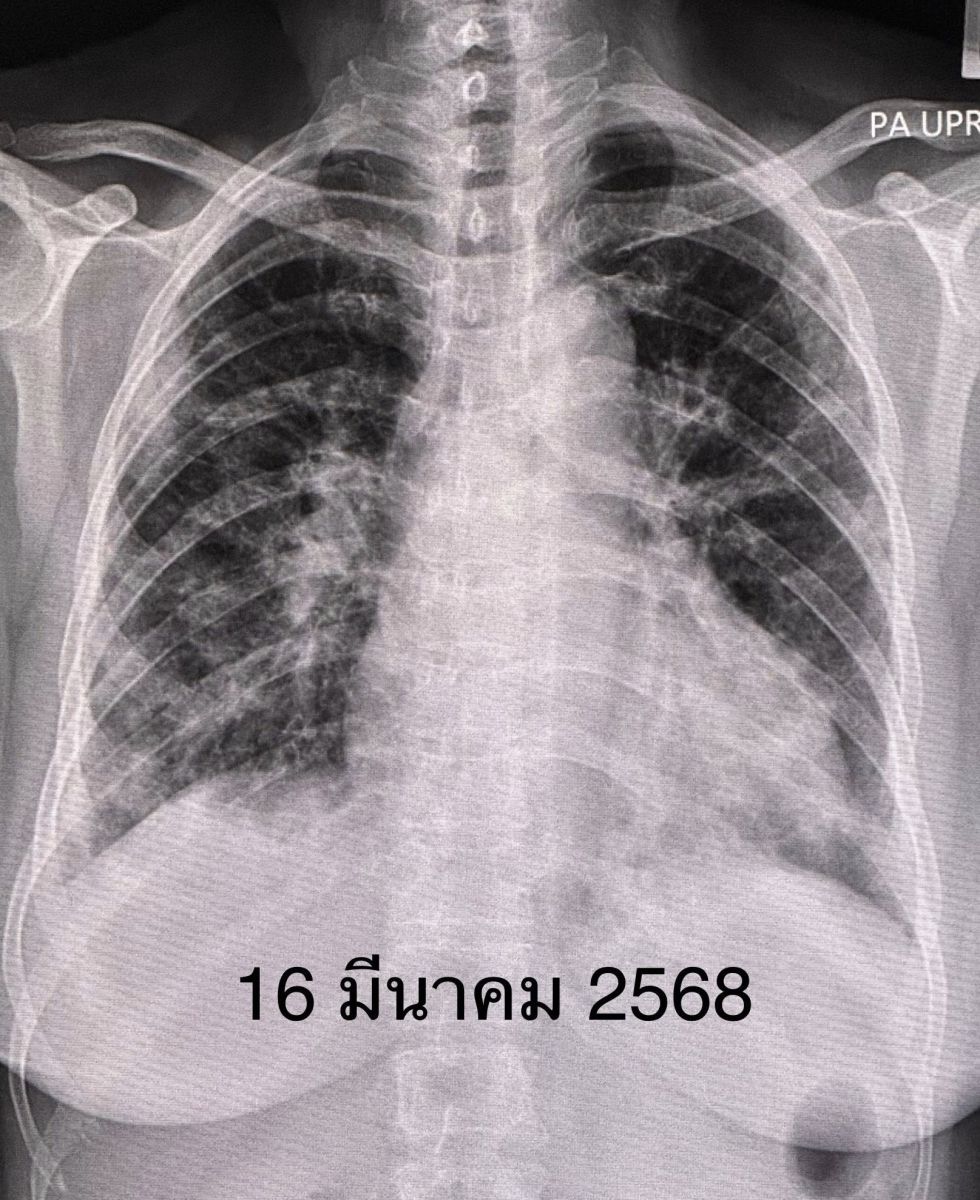

จนเริ่มเข้าโรงพยาบาลใกล้บ้านวันที่ 16 มี.ค.68 เพราะเหนื่อยมากขึ้นจนลุกขึ้นยืนไม่ได้ ไม่มีไข้ ผิวหนังปกติ กล้ามเนื้อไม่อ่อนแรง แต่ระดับออกซิเจนที่ปลายนิ้วต่ำมาก จนต้องให้ออกซิเจนชนิดอัตราการไหลสูงทางจมูก High-Flow nasal O2 cannula เจาะเลือด พบเลือดจางเล็กน้อย ค่าอักเสบในเลือด ESR และ hs-CRP สูง, ANA ปกติ ค่าโซเดียมในเลือดต่ำ เอกซเรย์ปอดและคอมพิวเตอร์ปอดพบปอดอักเสบทั้ง 2 ข้าง แยงจมูก ส่งเลือดเพาะเชื้อ ส่องกล้องเข้าไปในหลอดลม ไม่พบการติดเชื้อแบคทีเรีย ไวรัส เชื้อรา หรือวัณโรค ได้ยาปฏิชีวนะ เอกซเรย์ปอดไม่ดีขึ้น หลังรักษารพ.ใกล้บ้านมา 26 วัน ญาติขอย้ายมารักษาต่อวันที่ 11 เม.ย.68